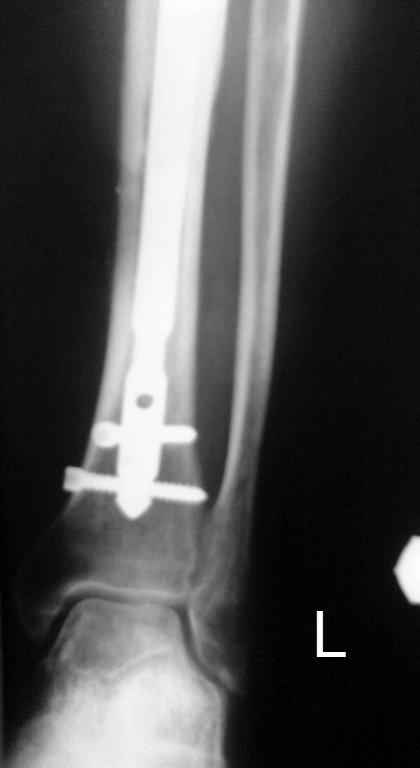

Итак, в настоящий момент больной пришел к нам с полной нагрузкой на оперированную конечность и с такой картиной (см. приложение). Участок мягких тканей с передней стенкой нижней трети ББК, выгнил и представляет дефект 2×2,5 см. На перевязке - циркулярный(?) некроз костной трубки.

Пациенту за 70 лет. Мои соображения: 1 этап - резекция tibia + косая остеотомия fibula + «острое» укорочение + IM цемент-гвоздь с а/б + beads. 2 этап (по заживлению раны) – удаление цемент-гвоздя + (LATN) Lengthening and Then Nailing. Прошу помощи по тактике.Никита Заднепровский